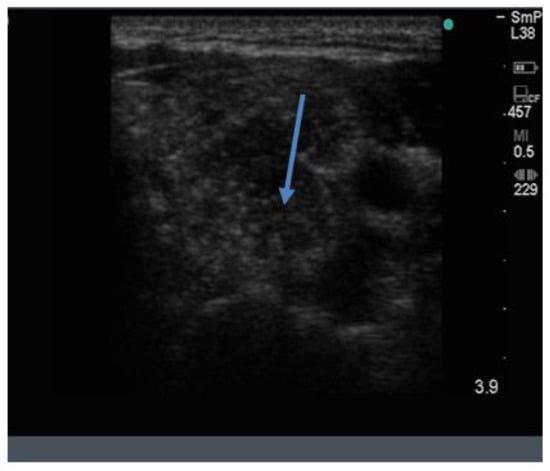

Because the senior author (JW) routinely measures serum calcium, parathyroid hormone (PTH) and vitamin D in his patients, hyperparathyroidism due to a benign adenoma of one of the parathyroid glands appears to be much more common than previously thought. The parathyroid glands are hidden behind the thyroid and so may be obscured by thyroid nodules, although they can often be seen in the longitudinal view below the lobes, as a hypoechoic lesion of around 1 cm in diameter (Figure 18).

Figure 18.

Thyroid ultrasound from a patient with hyperparathyroidism showing a hypoechoic lesion below the right thyroid lobe that was confirmed to be a parathyroid adenoma at surgery.

The parathyroid adenoma is typically hypoechoic by comparison to the nearby thyroid tissue, which is consistent with the author’s experience. However, only about 50% of subsequently proven parathyroid adenomas are seen on ultrasound and even the Sestamibi nuclear scan fails to pick them up in about 30% of cases.